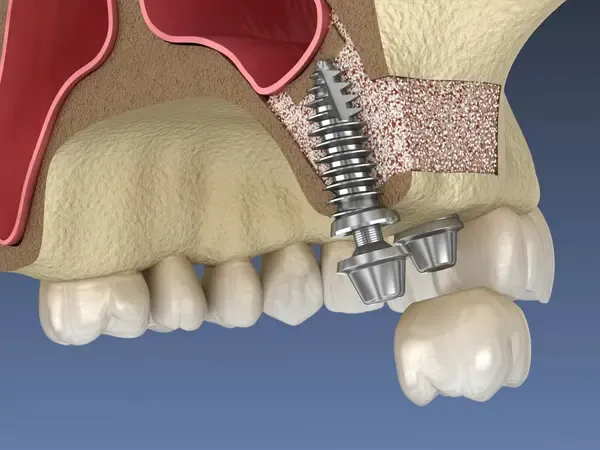

Implantul dentar este o piesă din titan pur, având, în general, forma de șurub. El are menirea de a crea o rădăcină artificială în osul maxilar, acolo unde dintele sau dinții naturali lipsesc. Reconstrucția este formată din două segmente — unul intra-osos (implantul) și unul supra-osos numit bont protetic. Deasupra bontului protetic se ancorează o coroană, o punte sau o proteză. Tratamentul este conservator în comparație cu o lucrare tradițională prin punte, deoarece implanturile dentare elimină necesitatea sacrificării dinților învecinați. În cazul în care confecționăm o punte dentară, aceasta are nevoie pentru ancorare de minimum 2 dinți stâlpi, dinți ce vor fi din păcate sacrificați (se extrag nervii, se obturează canalele și se șlefuiesc dinții care odinioară erau sănătoși).

Augmentarea osoasă (adiția de os) este o procedură stomatologică ce restabilește volumul osos maxilar/mandibular resorbit, necesară pentru fixarea stabilă a implanturilor dentare. Aceasta utilizează materiale autogene (de la pacient), sintetice sau osoase, deservind ca bază solidă pentru reconstrucția osoasă, adesea însoțită de o membrană de protecție.

Cea mai răspândită intervenție de augmentare osoasă în stomatologie este operația de sinus lift (ridicarea sinusului) – o procedură chirurgicală de adiție osoasă realizată la maxilarul superior pentru a crește volumul osos necesar inserării implanturilor dentare. Prin ridicarea membranei sinusale și introducerea unui material de grefare, se creează o bază solidă, fiind necesară când sinusurile sunt prea coborâte sau osul este prea subțire. Scopul acestei proceduri este crearea unui suport stabil pentru implanturi dentare în zona laterală superioară (molari/premolari). Procedura de adiție osoasă se efectuează sub anestezie locală. Vindecarea durează de obicei între 4 și 6 luni.